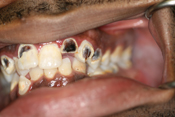

WORST TEETH Pictures from Warren Dentistry

This can happen to your teeth when proper Dental Hygiene is not practiced.

Patient 2